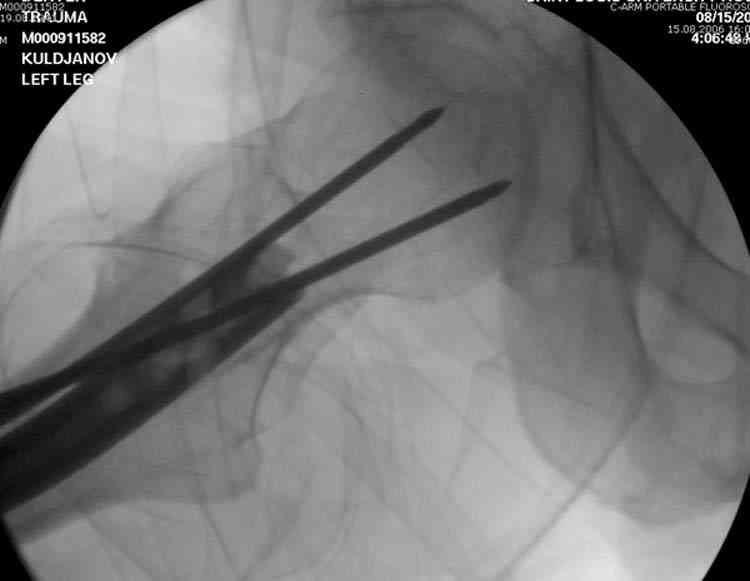

На второй день (7) обнаружен пропущенный перелом,

сделаны Компьютерная Томограмма

и проведены шурурпы через и спереди штифта без удаления.

Послеоперационные снимки